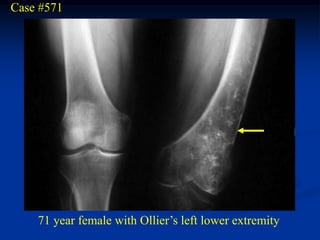

Multiple Enchondromatosis (Ollier’s)

Multiple enchondromatosis or Ollier’s disease, is a rare non-

familial cartilagenous dysplasia that is typically seen on one half

of the body and appears similar to fibrous dysplasia. Extensive

disease of the metaphyseal areas of long bone can result in bowing

and shortening. In the case of the femur a major bowing is seen

distally compared to the proximal bowing seen in fibrous dysplasia.

The cortical thinning and epiphyseal involvement seen in Ollier’s

disease is rarely seen in solitary enchondromas. The chance for

malignant conversion to a low grade chondrosarcoma in adult life

is about 25%.

Case #571

71 year female with Ollier’s left lower extremity

Lateral view of knee